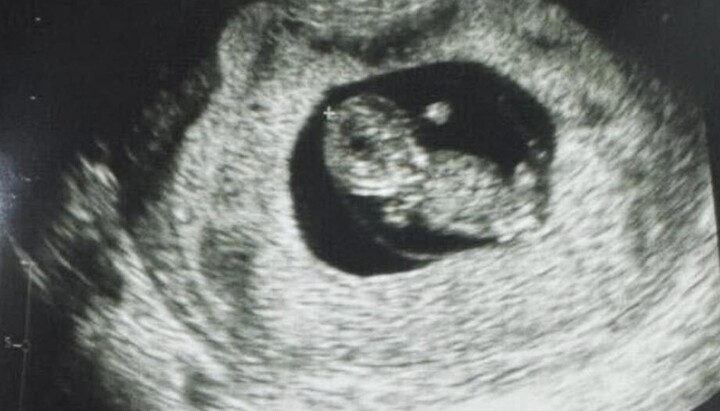

Αυτή την εβδομάδα στην κλινική Santa Isabel στην πρωτεύουσα του Περού Λίμα γεννήθηκε το πρώτο μωρό, στη γονιμοποίηση του οποίου το ωάριο ωρίμαζε έξω από το σώμα. Το Business Wire αναφέρει σχετικά, παραπέμποντας σε δήλωση της αμερικανικής εταιρείας βιοτεχνολογίας Gameto, η οποία ανέπτυξε αυτήν την τεχνολογία.

Η νέα προσέγγιση ονομάζεται Fertilo. Η εταιρεία ισχυρίζεται ότι υποτίθεται ότι είναι πιο ασφαλές για τις γυναίκες και πιο προσιτό από την παραδοσιακή εξωσωματική γονιμοποίηση (IVF).

Όπως εξήγησε η Gameto, με αυτή τη μέθοδο, η διαδικασία ωρίμανσης λαμβάνει χώρα έξω από το σώμα της γυναίκας με τη βοήθεια των λεγόμενων κυττάρων υποστήριξης των ωοθηκών που λαμβάνονται στο εργαστήριο από βλαστοκύτταρα. Οι προγραμματιστές ισχυρίζονται ότι η νέα τεχνολογία μπορεί να αντικαταστήσει έως και το 80% των ορμονικών ενέσεων που απαιτούνται για την παραδοσιακή εξωσωματική γονιμοποίηση.